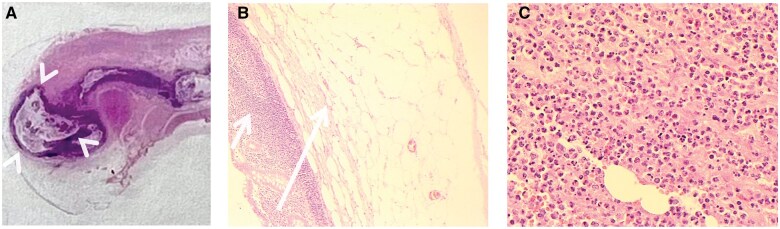

阑尾憩室炎,虽然罕见,是一个重要的鉴别诊断的情况下,右髂窝疼痛。以前,由于其临床表现相似,常被认为是急性阑尾炎的一种变体。然而,最近的研究表明,阑尾憩室炎是一个独特的临床实体,具有不同于急性阑尾炎的人口学特征和临床特征。它还与严重发病和死亡的高风险相关,需要及时诊断和管理。在此报告中,我们报告了一例58岁男性蚓状阑尾憩室炎患者,并回顾了相关文献。我们描述的分类阑尾憩室病和憩室炎,他们的临床表现,和他们的潜在并发症。我们概述了阑尾憩室炎和急性阑尾炎的影像学表现,并讨论了诊断成像在区分这两种疾病中的重要作用。

Appendiceal diverticulitis, although rare, is an important differential diagnosis in cases of right iliac fossa pain. Previously, it has often been considered as a variant of acute appendicitis, due to its seemingly similar clinical presentation. However, recent research indicates that appendiceal diverticulitis is a distinct clinical entity, with demographic characteristics and clinical features that are different to acute appendicitis. It is also associated with higher risk of severe morbidity and mortality, necessitating timely diagnosis and management. In this report, we present a case of a 58-year-old male patient with diverticulitis of the vermiform appendix and review the relevant literature. We describe the classification of appendiceal diverticulosis and diverticulitis, their clinical presentation, and their potential complications. We outline the radiological findings of appendiceal diverticulitis and acute appendicitis and discuss the important role of diagnostic imaging in distinguishing between these 2 conditions.